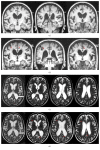

Idiopathic normal pressure hydrocephalus (iNPH) is the most common cause of hydrocephalus in adults. The diagnosis may be challenging, requiring collaborative efforts between different specialists. According to the International Society for Hydrocephalus and Cerebrospinal Fluid Disorders, iNPH should be considered in the differential of any unexplained gait failure with insidious onset. Recognizing iNPH can be even more difficult in the presence of comorbid neurologic disorders. Among these, idiopathic Parkinson's disease (PD) is one of the major neurologic causes of gait dysfunction in the elderly. Both conditions have their peak prevalence between the 6th and the 7th decade. Importantly, postural instability and gait dysfunction are core clinical features in both iNPH and PD. Therefore, diagnosing iNPH where diagnostic criteria of PD have been met represents an additional clinical challenge. Here, we report a patient with parkinsonism initially consistent with PD who subsequently displayed rapidly progressive postural instability and gait dysfunction leading to the diagnosis of concomitant iNPH. In the following sections, we will review the clinical features of iNPH, as well as the overlapping and discriminating features when degenerative parkinsonism is in the differential diagnosis. Understanding and recognizing the potential for concomitant disease are critical when treating both conditions.